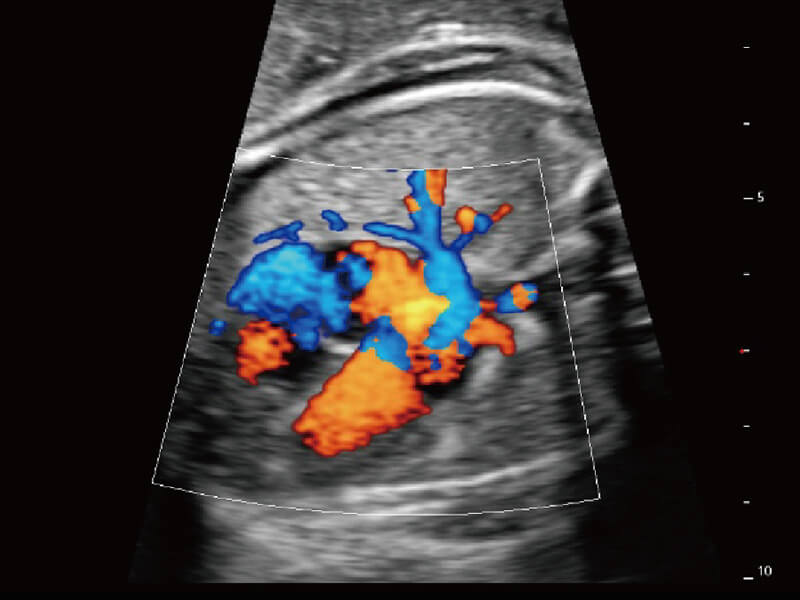

成像功能

性能优异的硬件架构,极大提升超声系统的运行效率和数据处理能力。相比以往超声成像系统,Wis+平台为您带来极快的响应速度和成像帧频,提升检查流畅度。

S60探头工艺,从前端信号处理每一个环节采集无损声学数据,真实还原组织原貌,再现解剖细节。